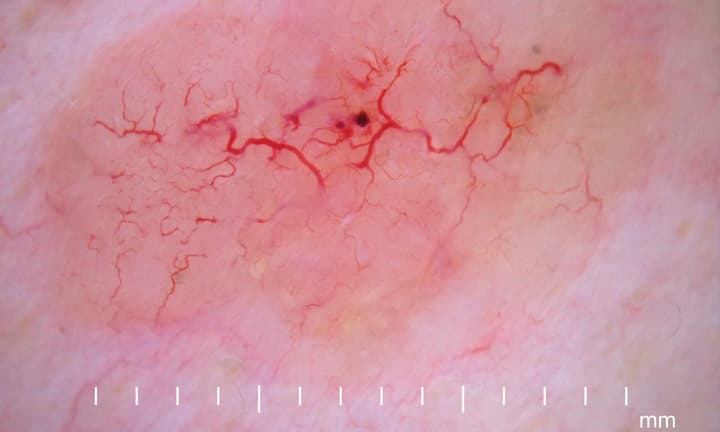

Dermatoskopie eines etwa 16 mm grossen nodulären Basalzellkarzinoms mit teleangiektatischen Gefässen.